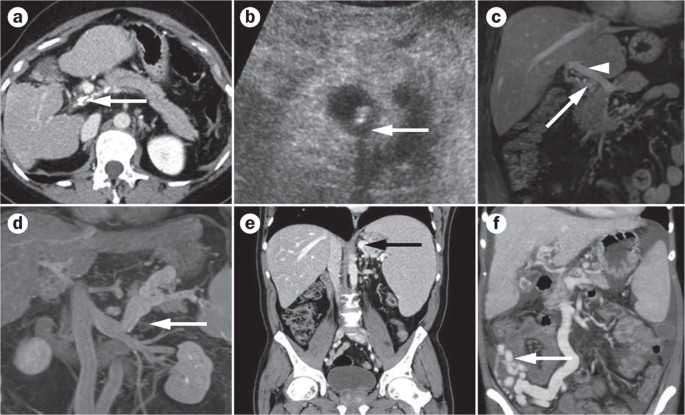

Imaging In Clinical Decision Making For Portal Vein Thrombosis Nature Reviews Gastroenterology Hepatology